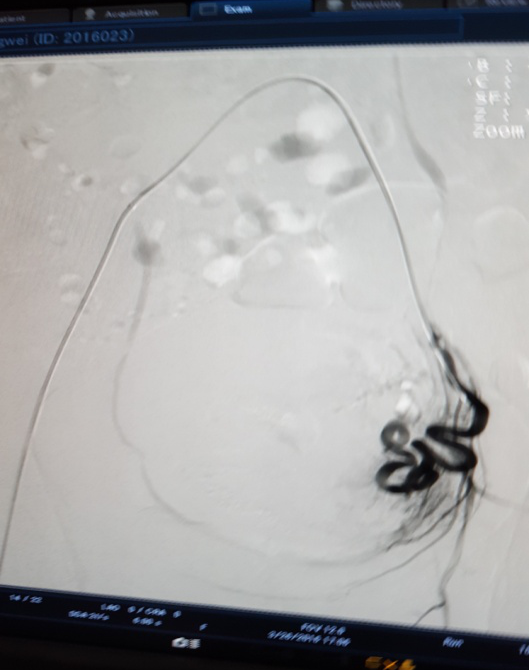

治疗前 左侧                              治疗后左侧分支血管消失

3月28日下午3点,在医院新导管室内,放射介入科主任张敏荣与任长德、李可峰医师成功地完成了新导管室建成后首例子宫腺肌症介入手术。该患者女性、40岁,因患子宫腺肌症,造成腹痛难耐,C臂下造影见:左子宫动脉增粗,分支数量增多、迂曲,用PVA颗粒栓塞迂曲的分支动脉,在妇产科保驾下,手术操作顺利。经过几天的对症治疗,各项检查指标符合出院标准,现病人已出院家中休养。该项手术的成功开展,又一次填补了市中医院该项之空白。